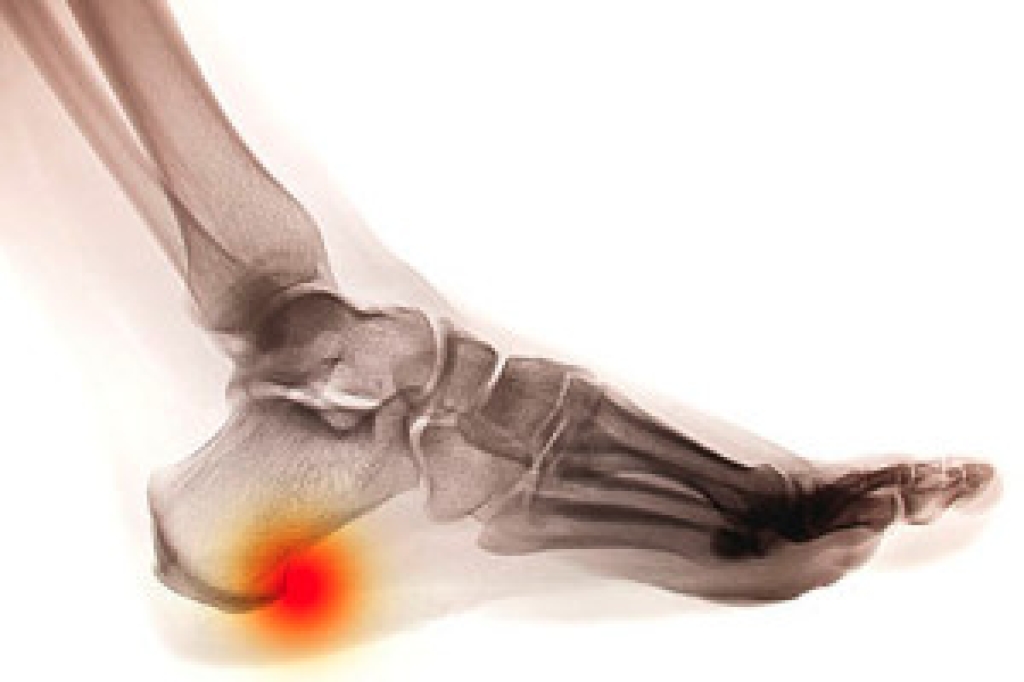

A heel spur is a bony growth that forms on the underside of the heel bone, often causing significant discomfort. This condition typically arises from repetitive stress or strain on the foot, which can lead to inflammation of the plantar fascia, the ligament that supports the arch. Risk factors can include obesity, prolonged standing, improper footwear, and activities that put excessive pressure on the feet. The main symptom is sharp, stabbing pain in the heel, particularly during the first steps in the morning or after periods of rest. To prevent heel spurs, it is essential to wear supportive shoes, maintain a healthy weight, and avoid excessive strain on the feet. Stretching exercises for the Achilles tendon and the plantar fascia can also help reduce the risk of developing this condition. If you have heel pain, it is suggested that you promptly schedule an appointment with a podiatrist who can accurately diagnose and treat heel spurs.

Heel spurs are formed by calcium deposits on the back of the foot where the heel is. This can also be caused by small fragments of bone breaking off one section of the foot, attaching onto the back of the foot. Heel spurs can also be bone growth on the back of the foot and may grow in the direction of the arch of the foot.